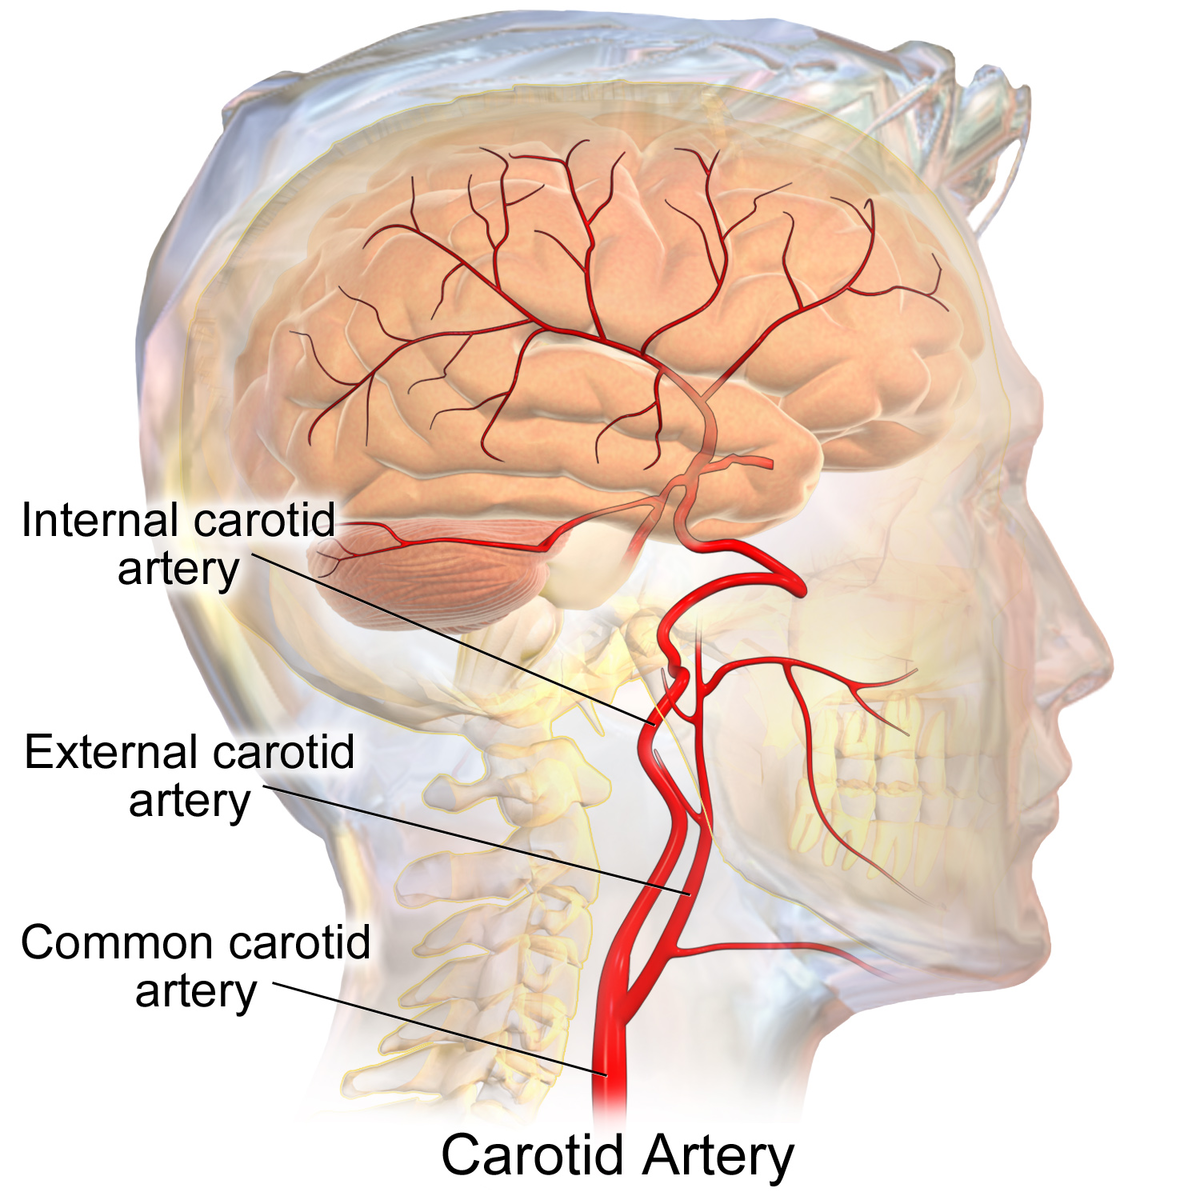

I think that severing the vagus and the carotid at the same time wouldn't allow enough time for the vagus to send the information to the heart in time to have in affect blood pressure in time to prevent any spurt. I could be wrong, but I think the blood pressure would have to be severely diminished, and I think that takes more time than lowering the blood pressure by bleeding out.